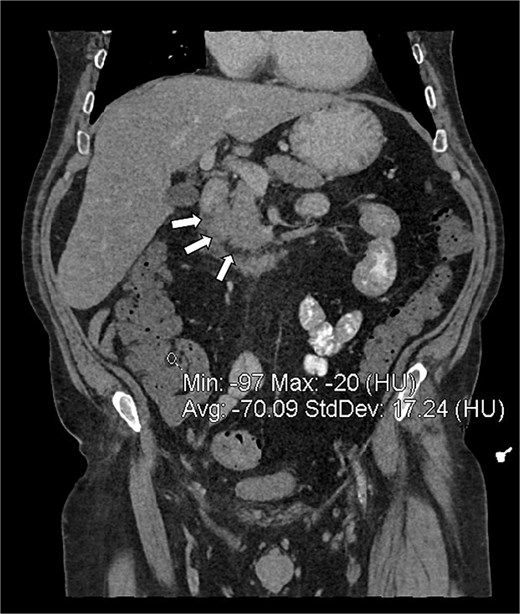

CTAP showed focal inflammatory fat stranding and minor un-encapsulated fluid around and between the second and proximal third parts of the duodenum, with an eccentrically thickened medial wall. The inflammation extended to involve the head and uncinate process of the pancreas (Figs 3 and 4). Acute groove-type pancreatitis is the favored diagnosis given the elevated amylase levels. However, acute duodenitis remains a differential diagnosis. Additionally, mural fat in the caecum and ascending colon was observed, consistent with chronic Crohn’s disease (Fig. 4), and a right-sided fat-containing inguinal hernia was also noted (Fig. 5).

Coronal reconstruction of abdominal CT showing inflammatory fat stranding (arrows) in the pancreaticoduodenal groove, between the duodenum and the uncinate process of the pancreas.